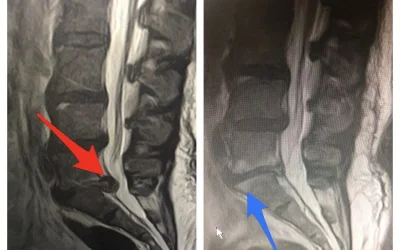

Estenosis severa de columna

El siguiente caso es de una paciente intervenida recientemente por una estenosis severa en la columna lumbar, nivel L4-L5. La estenosis en la columna...